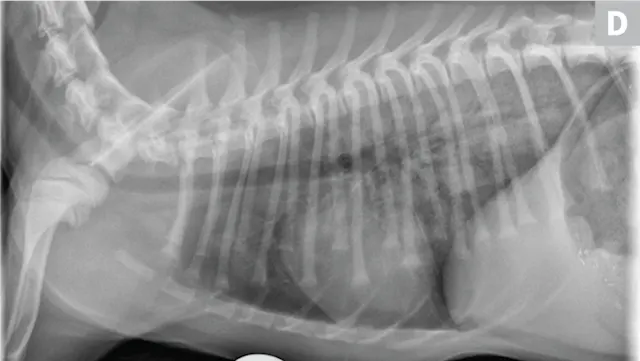

Eosinophilic bronchopneumopathy (EB) is an idiopathic inflammatory hypersensitivity disorder associated with acute onset coughing, gagging, retching, and/or respiratory distress. Radiographs may reveal a diffuse bronchointerstitial pattern or alveolar disease (Figure 3). Patients with EB have airway cytology supportive of eosinophilic inflammation and are negative for parasitic testing.

FIGURE 3

Eosinophilic bronchopneumopathy. Note the heavy, patchy bronchointerstitial pattern.